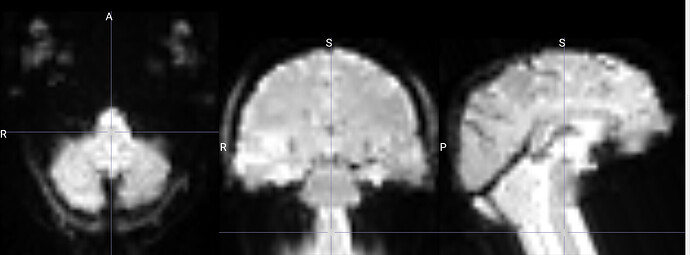

I am running fmriprep for the first time, and my preproc_bold.nii files have a weird distortion extending from the cerebellum for a few slices, it is basically a copy of what seems like the final slice, extending anteriorly.

The copied slices are overlapping with the superior slices, likely messing with the voxels.

images showing how it extends anteriorly: